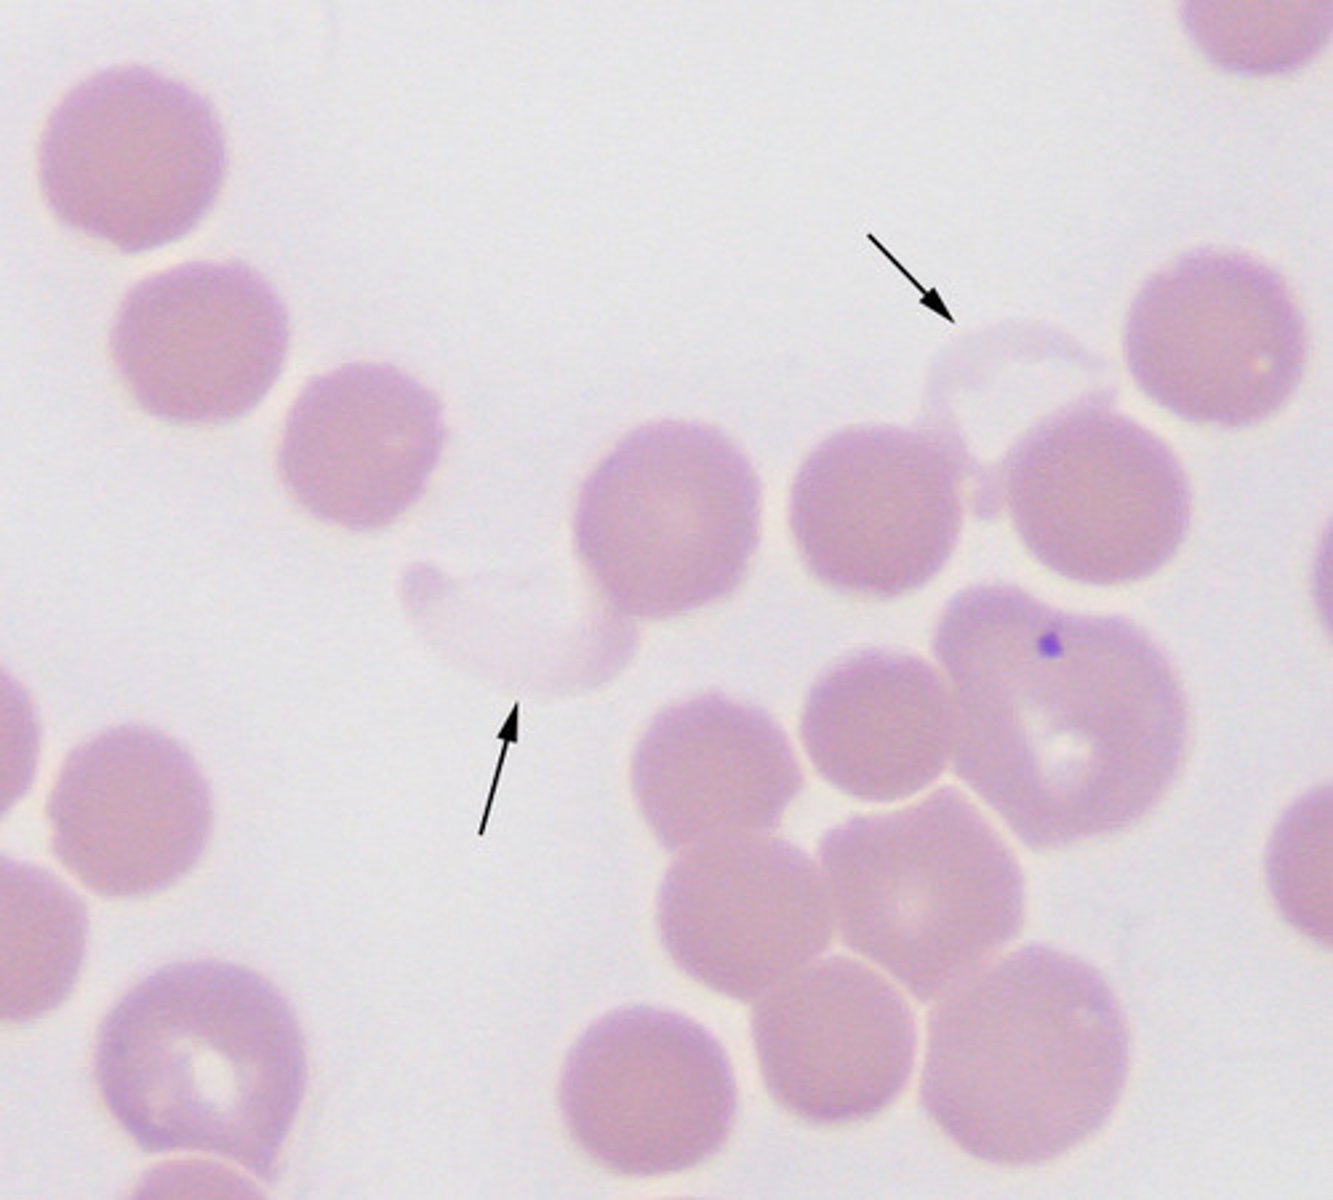

anaplasma

exotic

intracytoplasmic inclusions

trypanosomes

exotic

haemoproteus

exotic hemoparasite

nucleus is "embraced" not "displaced"

via blood sucking insects